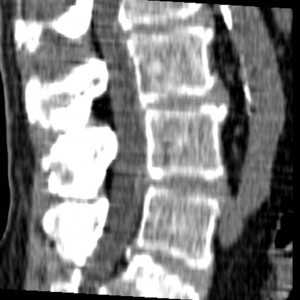

*Грыжа Шморля на МРТ снимке.